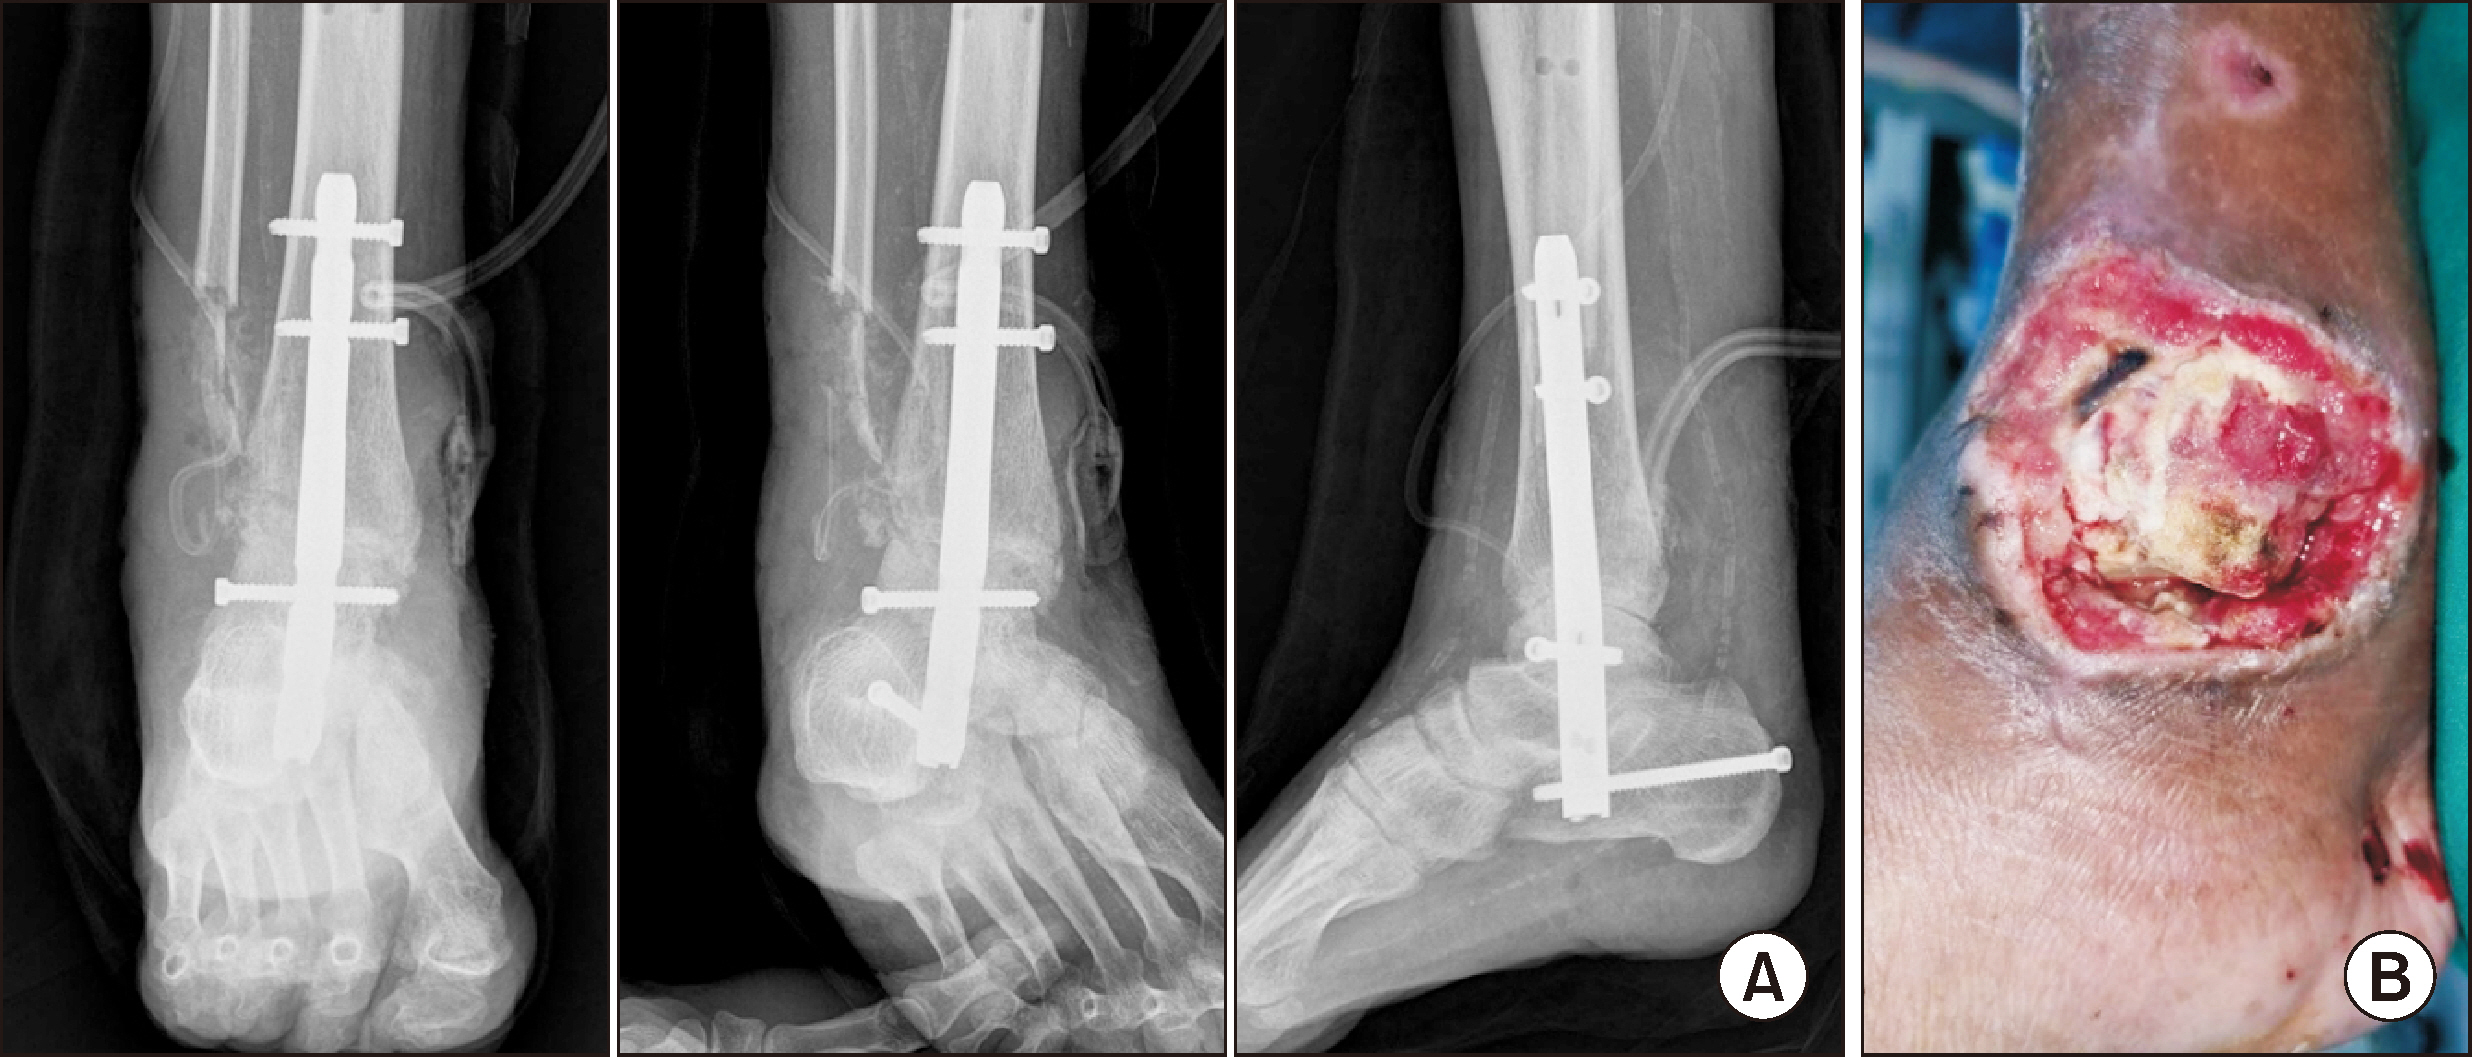

Comprehensive Management of Presumed Underlying Charcot Arthropathy with a Subsequent Traumatic Ankle Fracture in a Patient with Diabetes Mellitus, End-Stage Renal Disease: A Case Report

Charcot neuroarthropathy (CN), also known as Charcot arthropathy, is a complex, progressive disorder primarily affecting the foot and ankle. This case report describes a multifaceted management strategy for a 54-year-old male with diabetes mellitus, end-stage renal disease, and presumed underlying Charcot arthropathy who experienced a traumatic ankle fracture. The initial surgical plans were delayed because of systemic infection indicators, including elevated C-reactive protein levels and high fever. The patient underwent multiple surgical interventions and faced challenges, including metal failure, implant-associated infection, and tibiotalar joint dislocation. A multidisciplinary approach involving orthopedic surgeons, nephrologists, and endocrinologists was crucial for managing the case effectively. In particular, the patient declined a below-knee amputation and opted for comprehensive surgical intervention, resulting in improved functionality at the latest follow-up. This case highlights the complexities of managing CN in patients with multiple comorbidities and emphasizes the need for a nuanced, patient-centered approach.